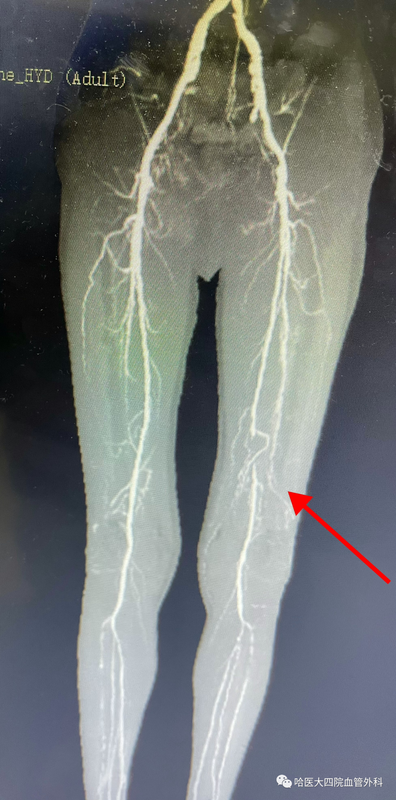

??近日,哈醫(yī)大四院血管外科為一名下肢動脈閉塞癥患者開通了血管,使用的手術方式是目前對于下肢動脈嚴重狹窄或閉塞疾病有良好效果的動脈斑塊旋切術。??62歲的孔大爺近幾年一直受腿疼的困擾,走個幾百米,小腿就疼,需要停下來歇會兒。尤其在冬天,腿疼癥狀更加嚴重,需要經(jīng)??诜?zhèn)痛藥物。家屬帶孔大爺來到哈醫(yī)大四院血管外科就診。經(jīng)檢查發(fā)現(xiàn)孔大爺患有下肢動脈閉塞,且閉塞位置在股腘動脈交界位置,該部位在膝蓋附近,由于膝關節(jié)經(jīng)?;顒?,所以這個部位不適合支架植入治療。?????????術前CTA示:左下肢股淺動脈閉塞??????經(jīng)過縝密的術前準備,血管外科團隊決定?應用Turbohawk斑塊旋切系統(tǒng)為患者開通閉塞血管。術中將帶有旋切刀片的導管送入病變部位的動脈腔內,通過高速的旋轉可以在通過病變中切除斑塊,該手術不僅直接清除斑塊,恢復血流,而且術后血管內不留下任何異物材料,減少術后血管內膜增生引起的再狹窄,術后孔大爺腿疼癥狀即刻消失。????????A?????????B????????C??????????A:術中造影示左側股淺動脈閉塞??????????B:旋切刀頭在閉塞血管內??????????C:斑塊旋切后血管恢復正常血流?????????????血管外科團隊為患者實施手術????????黃任平主任介紹,斑塊旋切技術是目前國內外治療下肢動脈閉塞的最先進、最有效的技術之一,因其可避免血管內支架植入后再閉塞處理困難等優(yōu)點,為廣大患者所接受,哈醫(yī)大四院血管外科團隊在省內率先開展此項技術,為下肢血管閉塞疼痛患者帶來福音。專家簡介黃任平主任醫(yī)師、醫(yī)學博士、博士后,碩士生導師哈爾濱醫(yī)科大學附屬第四醫(yī)院血管外科主任??專業(yè)方向:擅長血管外科的常見病多發(fā)病的診治,從事微創(chuàng)血管病治療與創(chuàng)面治療10余年,治愈各種靜脈曲張、糖尿病足、下肢靜脈血栓、脈管炎、動脈硬化閉塞癥、胸腹主動脈瘤、動脈栓塞、肺栓塞、鎖骨下動脈閉塞、腎動脈狹窄、嬰幼兒血管瘤、血管畸形等20000余例。???出診地點:哈爾濱醫(yī)科大學附屬第四醫(yī)院門診三樓C區(qū)外科3診室咨詢電話:0451-82576869